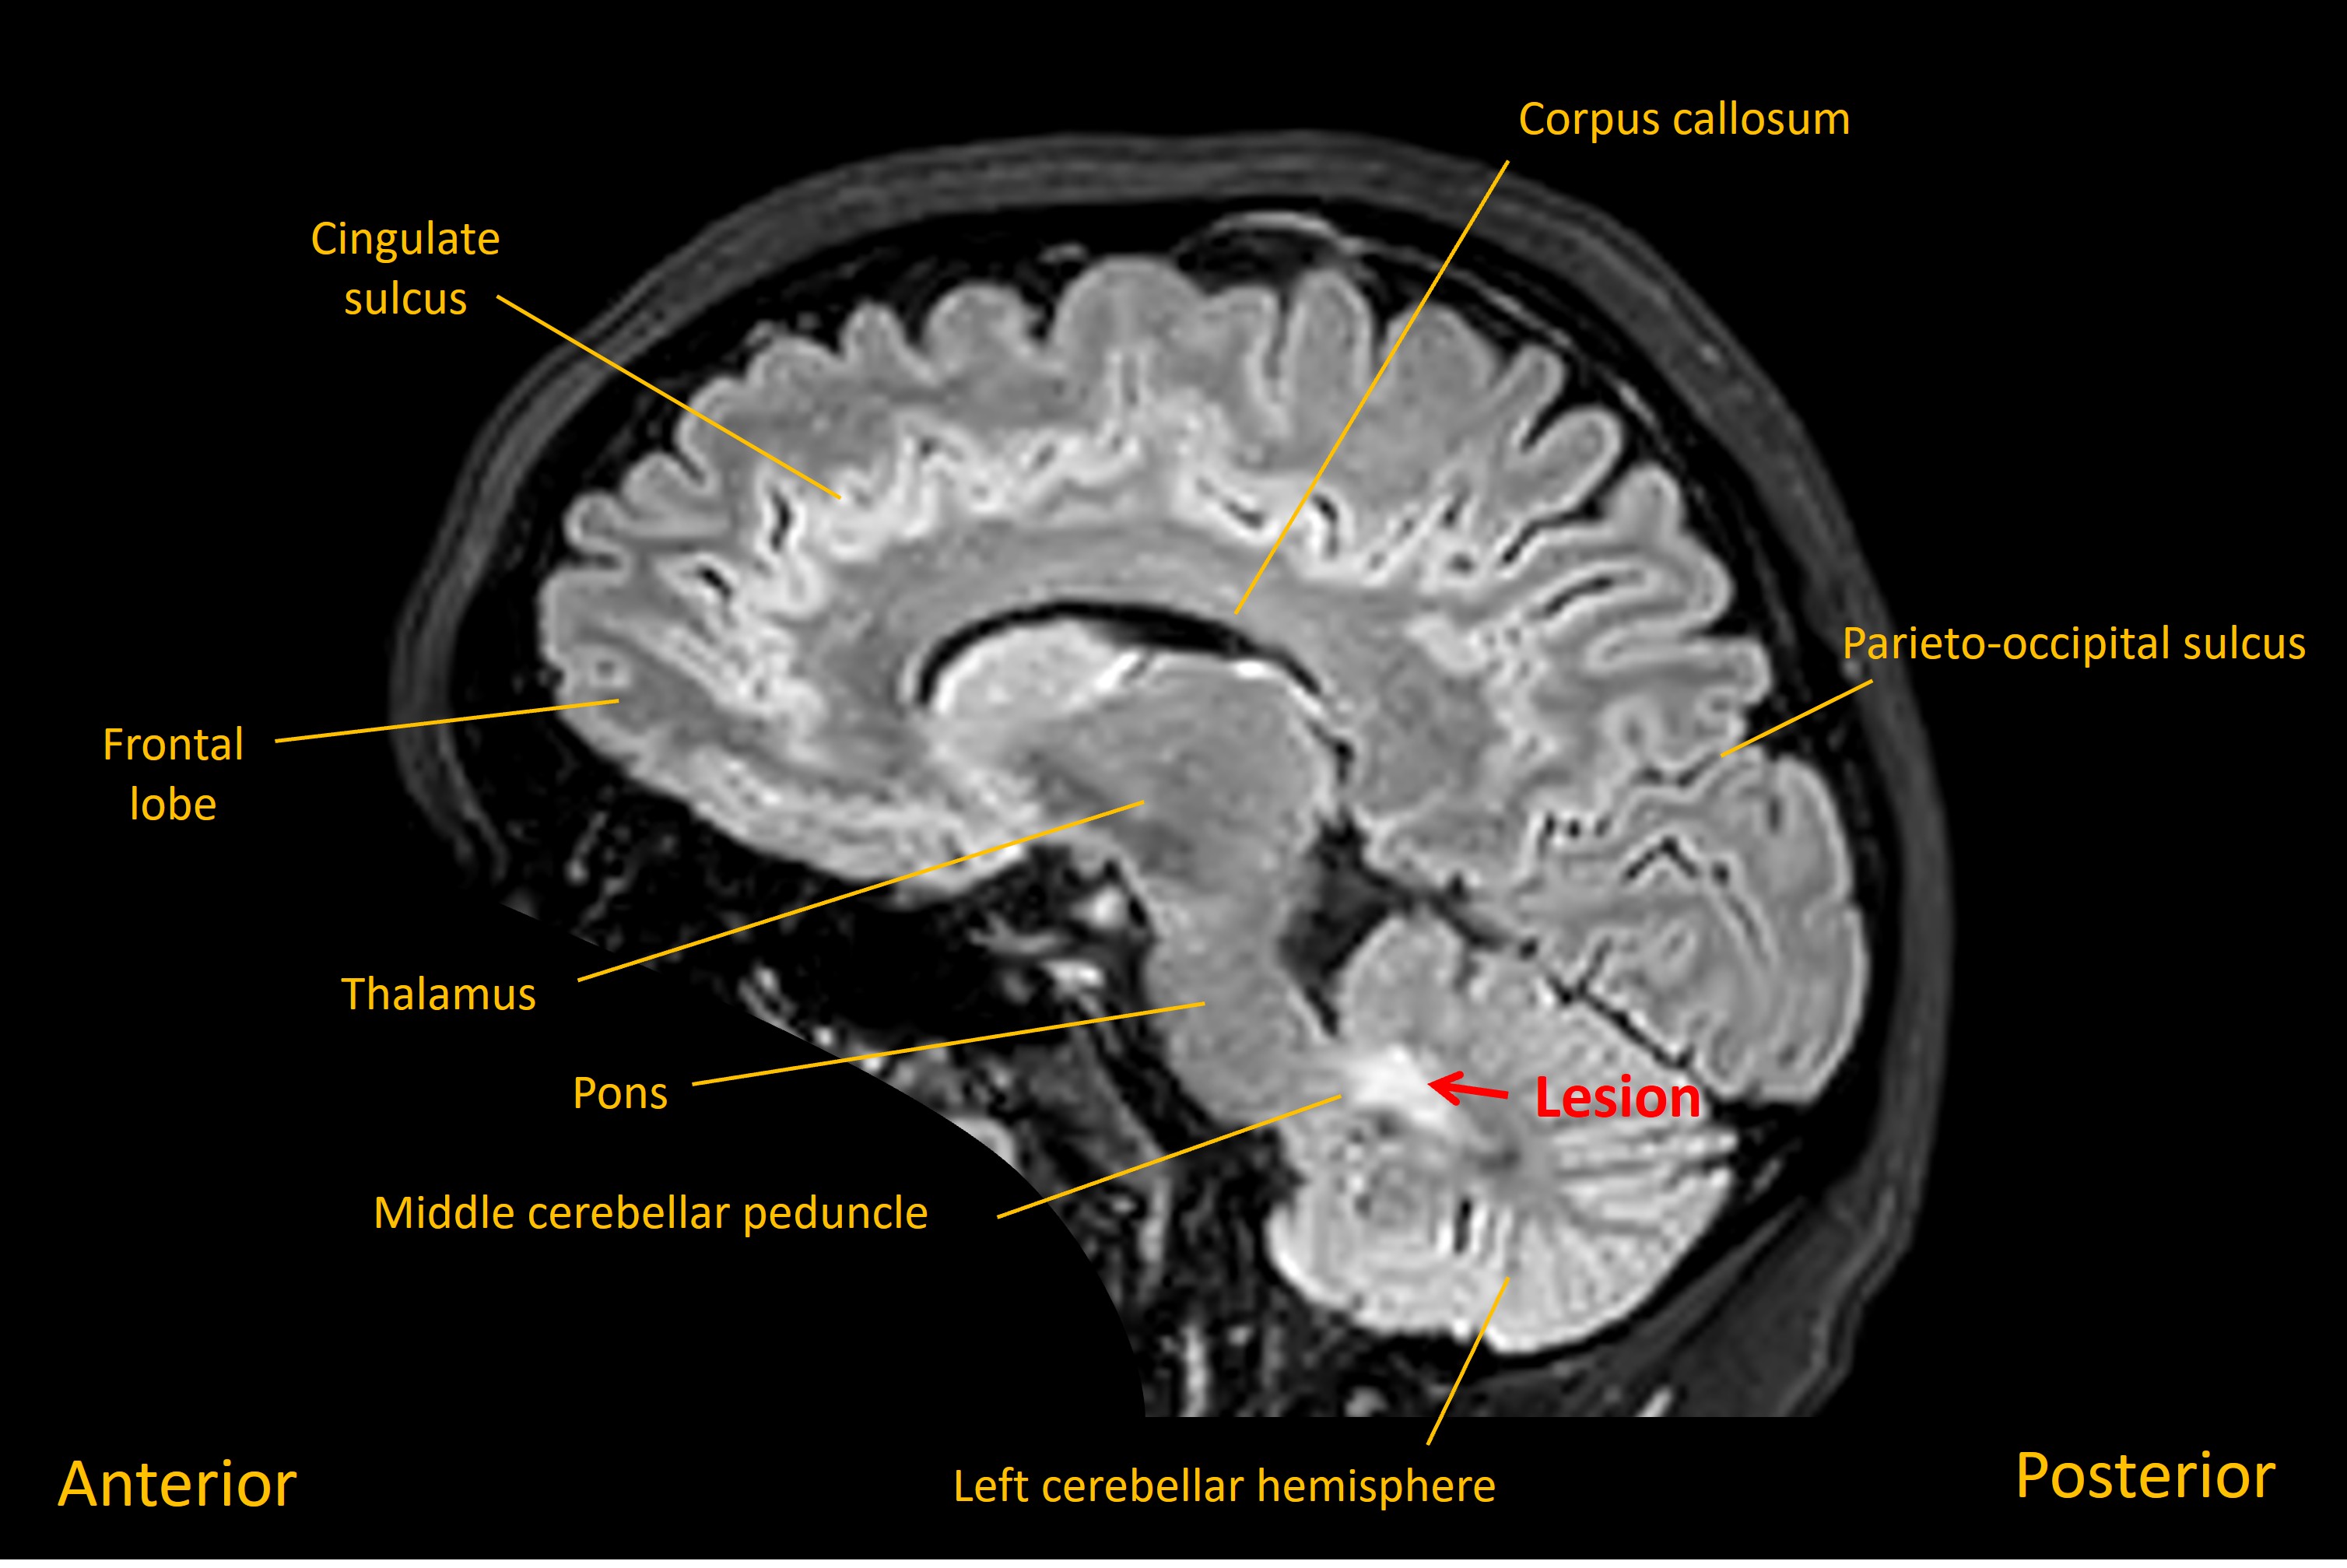

She was admitted and had an MRI brain which showed a lesion in the left middle cerebellar peduncle adjacent to the fourth ventricle. Imaging features suggested a solitary demyelinating lesion – and in the absence of other lesions, or prior symptoms, this was not in keeping with a diagnosis of multiple sclerosis (MS).